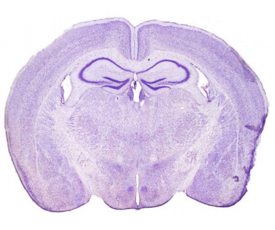

二、脑组织切面

脑组织的切面多种多样,最常用的有冠状面(coronal)、矢状面(sagittal)和水平面(horizontal)。

| 冠状切面(将脑分为前后两半):常见切面:前额叶皮层、纹状体 、小海马(经典海马)、大海马(黑质) | 矢状切面(将脑分为左右两半):可同时观察嗅球,皮层,纹状体,海马,小脑等;适合同一标本做不同实验左右对照 |

水平切面(将脑分为上下两半):可同时观察皮质、纹状体、海马、中脑、小脑等;看病理分布推荐水平切面 |